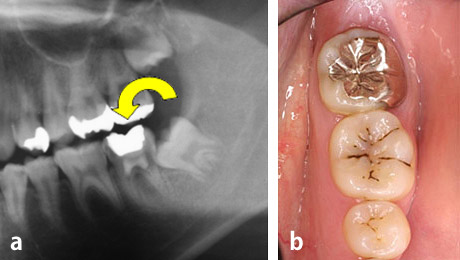

歯根完成歯親知らずの移植

左:治療前のCT画像。

右:治療前の口腔内。

24歳、女性。右下第二大臼歯部(受容側)へ親知らず(ドナー歯)を移植してほしいという希望で来院されました。

ドナー歯はすでに歯根が完成しています。このような場合、移植後に歯髄(神経)の治療が必要です。